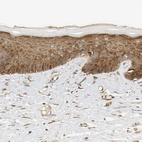

Immunohistochemical staining of human Fallopian tube shows weak to moderate cytoplasmic positivity in glandular cells.